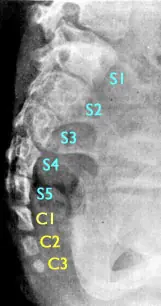

3-Cola Humana Verdadera (Cola Vestigial)

Frecuencia: Alrededor de 100 casos documentados en todo el mundo.

Causa: No se conoce en profundidad. Se cree que se produce por la mutación de los genes encargados de producir la muerte celular programa de las células que estaban destinadas a formar una cola.

Descripción: Se observa la presencia de una cola vestigial en la zona final del sacro, a nivel cóccix. Esta cola está compuesta de tejido conectivo, músculos, vasos sanguíneos, nervios, piel, vértebras y cartílago.